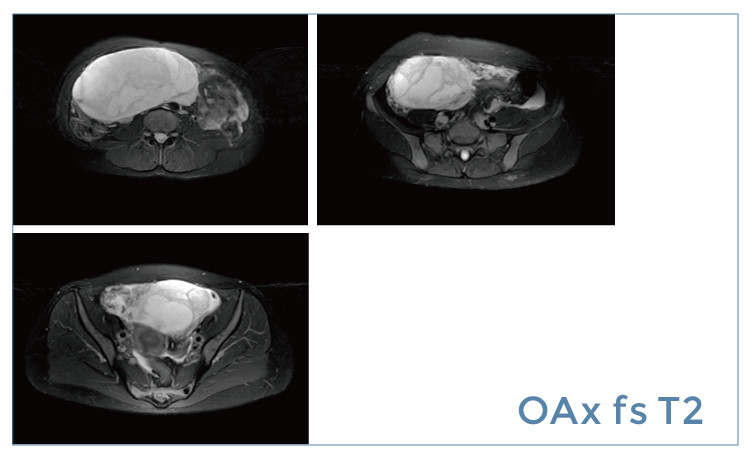

【朗润影像档案】磁共振影像病例分享(编号20190412)

【朗润影像档案】20190412磁共振影像病例结果讨论